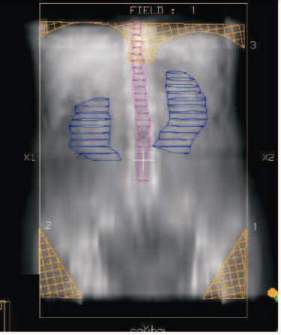

Cílový objem pro kurativní radioterapii zahrnuje celou dutinu břišní. K ozáření této rozsáhlé oblasti se historicky používala technika postupujících pruhů (moving strip - obr. č. 1), protože starší ozařovače nebyly schopny poskytnout pole dostatečné velikosti.

Obr. č. 1: Moving strip

Celá dutina břišní byla postupně ozářena pruhovým polem o maximální výšce 10 cm, které postupovalo v denních intervalech od dna malé pánve kraniálně. S érou moderních lineárních ozařovačů byla technika moving strip opuštěna ve prospěch otevřených polí, která umožňují denní ozáření celé peritoneální dutiny. Horní hranice cílového objemu je 2 cm nad kupolí bránice při klidném dýchání, dolní hranici tvoří dolní okraj foramina obturatoria. Laterální hranice jsou zvoleny 2 cm za laterální rozsah peritoneální dutiny (obr. č. 2).

Obr. č. 2: Technika otevřených polí s bloky

Dávky záření jsou limitovány tolerancí ledvin, jater a tenkého střeva na záření. Ledviny je nutné stínit vykrývacími bloky, aby dávka na nich nepřesáhla 18–20 Gy. Vzhledem k tomu, že peritoneální prostor mezi kupolí pravé bránice a horním povrchem jater je častým místem metastatického rozsevu, jsou celá játra zahrnuta v cílovém objemu. Jako zdroj záření je nutné použít vysokoenergetické záření (lineární akcelerátor), aby variace dávky uvnitř cílového objemu nepřesáhly 5 %. Dávka na celou dutinu břišní je limitována do 30 Gy při frakcionaci po 1–,5 na jednu frakci. Dávka na oblast malé pánve a paraaortální uzliny bývá doplňována do 45–50 Gy (1,8–2 Gy na jednu frakci). Doplnění dávky na malou pánev či paraaortální oblast však není univerzálně akceptováno, autoři vypouštějící zvýšení dávky na malou pánev argumentují menší incidencí pozdní gastrointestinální toxicity (35, 36).